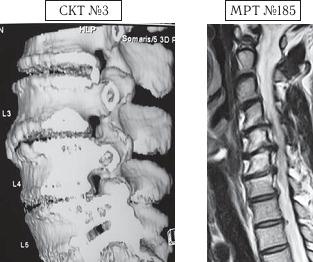

Примеры подобных случаев представлены на следующих снимках.

На спиральной компьютерной томографии № 3 хорошо видно сращение межпозвонковых дисков, за счёт их фибротизации.

На МРТ № 185 бывшего спортсмена (чемпиона-легко-атлета) видны тяжёлые последствия данного вида спорта в виде остеофитоза, спондилёза, стеноза спинномозгового канала с грубым сдавлением дурального мешка, гипертрофией как задней, так и передней продольных связок.

Как в первом, так и во втором случаях наблюдаются костные разрастания, срастания тел смежных позвонков, которые являются прямыми противопоказаниями к применению вертеброревитологии. Показания и противопоказания выявляются на первичной консультации, обязательно наличие у пациентов снимков магнитно-резонансной томографии (МРТ). Снимки компьютерной томографии (КТ) для данных целей, как правило не подходят, так как они менее информативны и не отражают в достаточной степени картину состояния позвоночника, если, конечно, речь идёт о показаниях к лечению методом вертеброревитологии.